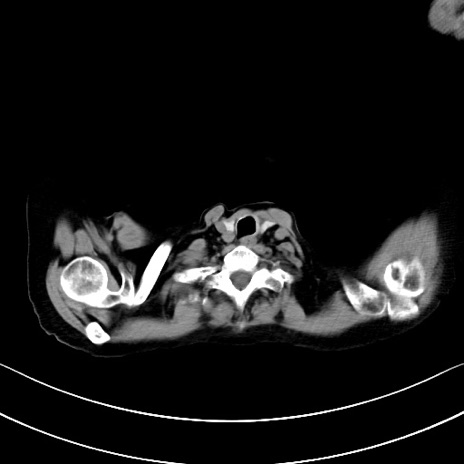

横断像

他院CT